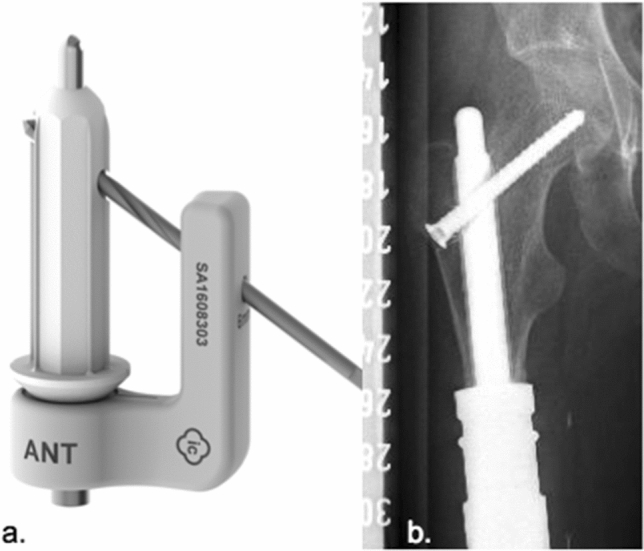

MUTARS® custom-made ultra-short proximal tibia stem (implantcast, Buxtehude, Germany) (Fig. 8)

Custom-made modular ultra-short proximal tibia stem: length and diameter adjustable depending on remaining bone stock. Non-cemented fixation: titanium–aluminum–vanadium alloy (ISO 5832-3), rough surface with hydroxyapatite coating (TCP also possible). Solid or hollow, hexagonal stem design with protruding fins and option of implantation of interlocking screw. Indication: epi- and metaphyseal proximal tibia. This stem design was first reported in 2017 [7].

Fig. 8.

Custom-made modular ultra-short proximal tibia stem (implantcast, Buxtehude, Germany)